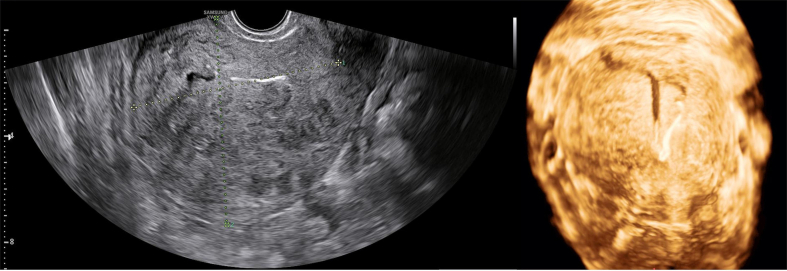

A 42-year-old woman with gravida 2 para 1, she had a regular menstrual cycle with an average amount of flow. She has moderate intensity periodic congestive dysmenorrhea and has previously required 1–2 painkillers during her menstrual period. But since 7 years ago, the intensity of her abdominal pain has been increasing, and an ultrasound examination indicates adenomyosis. The patient underwent curettage and had LNG-IUS placed in the uterine cavity six months ago due to excessive menstrual flow. After treatment, the menstrual flow was minimal, and the symptoms of dysmenorrhea disappeared. The patient was very satisfied with this treatment. The patient experienced vaginal bleeding again nine days ago and needs to replace four sanitary pads a day. She came to our hospital for treatment. A vaginal examination showed a small amount of dark red blood in the vagina, and an ultrasound examination showed that LNG-IUS had moved down. The size of the uterus is 88 × 85 × 79 mm, and the posterior wall of the uterus is an adenomyoma with a size of 84 × 53 mm. The intrauterine device is moved downwards, about 61 mm away from the serous layer of the uterine floor (Fig. 1). Based on the patient's medical history and ultrasound results, we provided various treatment options, including medical treatment, hysteroscopic ING-IUS suture, and laparoscopic hysterectomy, and explained the benefits and risks. After obtaining informed consent, an experienced chief physician performed a hysteroscopic LNG-IUS suture. The levonorgestrel release intrauterine device was sutured and fixed to the anterior uterine wall using an Intergrative Operative Hysteroscope surgical system and non-absorbable suture (Fig. 2). The surgical time is 30 min, with 5 ml of intraoperative bleeding and 5000 ml of distending media. After surgery, oral antibiotics (0.25 g of cefuroxime sodium twice a day for 3 days) were taken to prevent infection. At the 6-month postoperative follow-up, dysmenorrhea was relieved and menstrual flow decreased, and she informed us that there was no discomfort. The ultrasound shows that the uterus has shrunk to 76 × 76 × 78 mm, and the position of the contraceptive device is normal (Fig. 3).

Fig. 1.

The size of the uterus is 88 × 85 × 79 mm, and the posterior wall of the uterus is an adenomyoma with a size of 84 × 53 mm. The intrauterine device is moved downwards, about 61 mm away from the serous layer of the uterine floor.